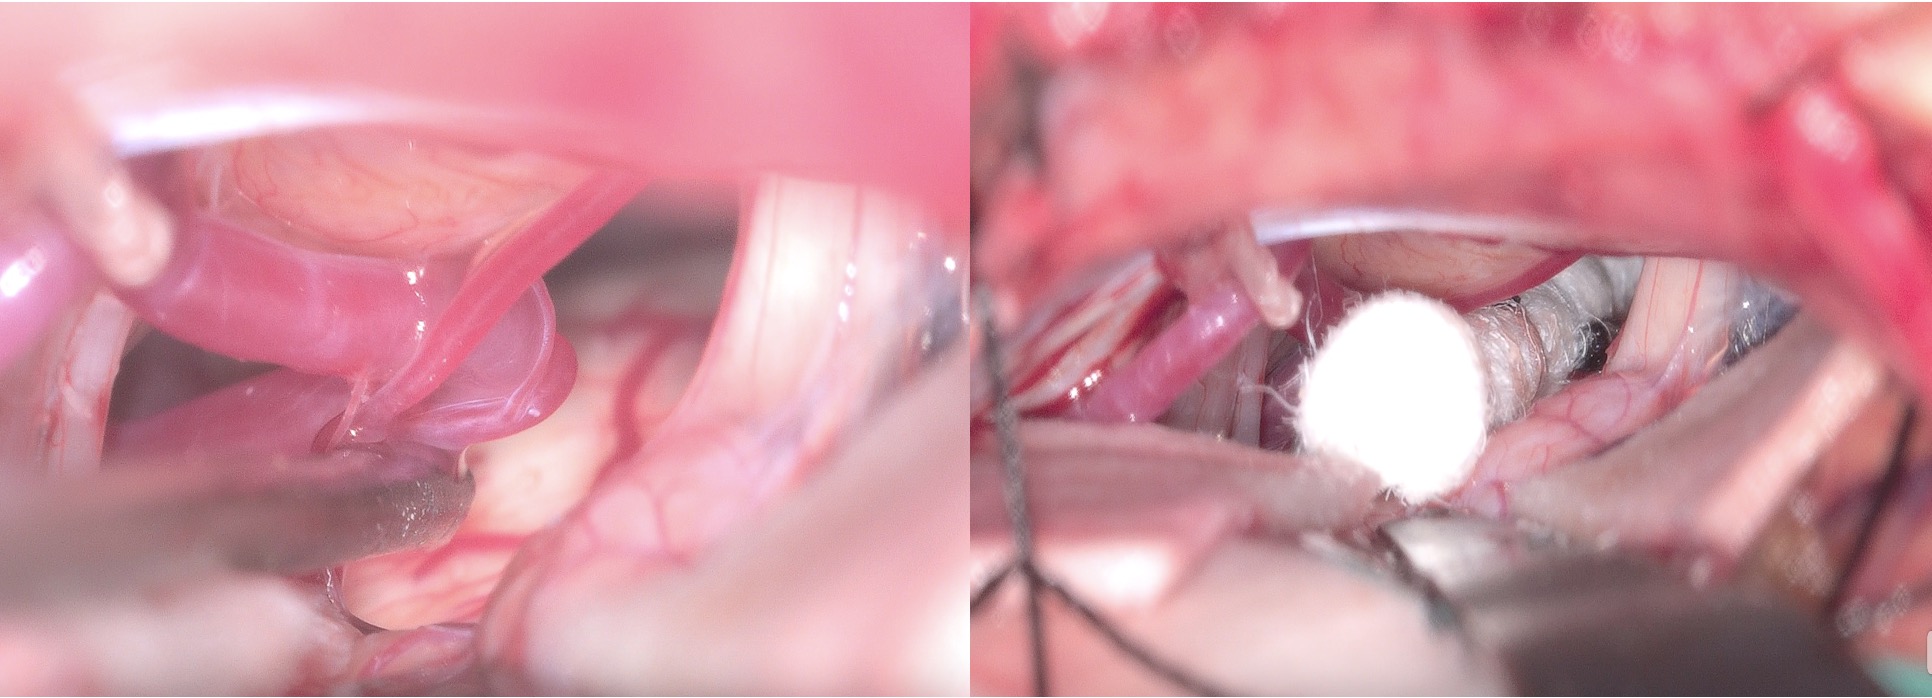

56歳女性、左顔面けいれんを手術しました。外視鏡-仰臥位でのCP angle手術も6回目を迎え、スタッフも慣れてきました。患者のセッティングについては、尾側への筋層牽引がもう少し強くできるとより快適に手術ができるように思われ、まだ改善できそうです。今回はTranspositionでAICA-PICA complexを動かしましたが、顔面神経に直行するように走行する部分の持ち上がりが悪かったので、Bridge technique (Inoue T et al: Acta Neurochirurgica (2021) 163:3311–3320) を用いました。けいれんは手術直後より完全消失、しばらく眩暈がありましたが軽快し、合併症(顔面まひ、聴力消失その他)なく退院されました。